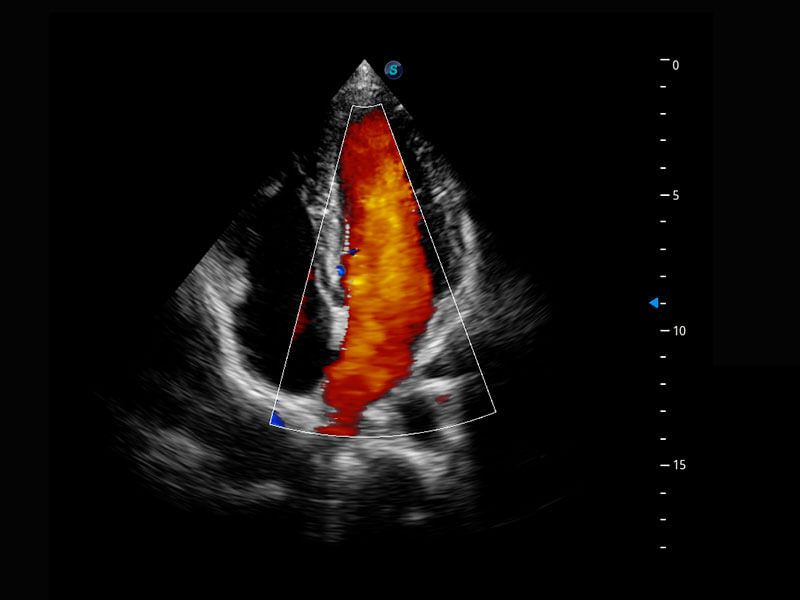

P60搭载宽频带线阵探头、宽景成像、弹性成像技术,为您提供乳腺应用方案。P60支持高频相控阵探头、线阵探头、腹部高频探头、腹部微凸探头等,丰富的探头群搭载敏感的彩色血流成像,适用于新生儿多种脏器检测要求,满足新生儿筛查需求。

新生儿心脏